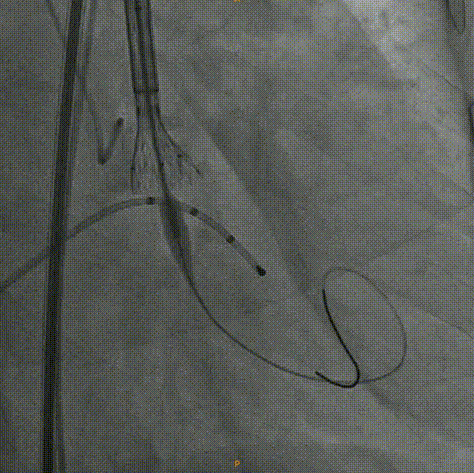

Venus26号瓣膜释放:前三分之一慢放精准定位,中三分之一快放使瓣膜快速进入工作状态。

Venus26号瓣膜释放:位置良好,轻度反流,遂完全释放后采取后扩。

后扩后瓣膜最终形态。